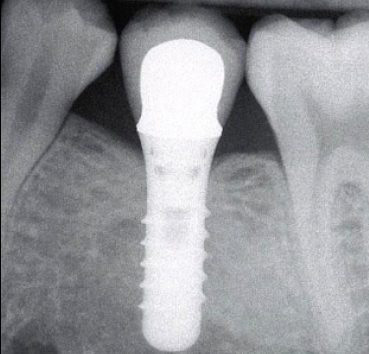

Les implants dentaires sont la solution la plus appropriée pour remplacer une dent manquante et la meilleure alternative aux bridges fixes, car ils évitent d'abaisser l'émail des dents adjacentes et permettent une hygiène naturelle. Réalisé par une équipe de dentistes experts à Valence, Espagne.

Les implants dentaires, qui agissent comme de puissants ancrages, permettent de réaliser des bridges implanto-portés lorsqu'il manque au moins trois dents. Fabriqué par une équipe de dentistes experts à Valence, en Espagne.

Les prothèses complètes ancrées sur implants évitent tous les inconvénients de ce type de prothèse, tels que la mobilité, les frottements et l'utilisation d'adhésifs coûteux et inconfortables. Fabriquées par une équipe de dentistes experts à Valence, en Espagne.

Les prothèses complètes vissées sur implants sont ce qui se rapproche le plus des dents naturelles, évitant l'utilisation de prothèses amovibles et leurs problèmes associés tels que la mobilité, le frottement ou l'utilisation d'adhésifs. Elles sont fabriquées par une équipe de dentistes experts à Valence, en Espagne.

La meilleure solution pour la plupart des cas est sans aucun doute les implants dentaires, Résumé de la technologie et des cas Mozo Grau Ticare.